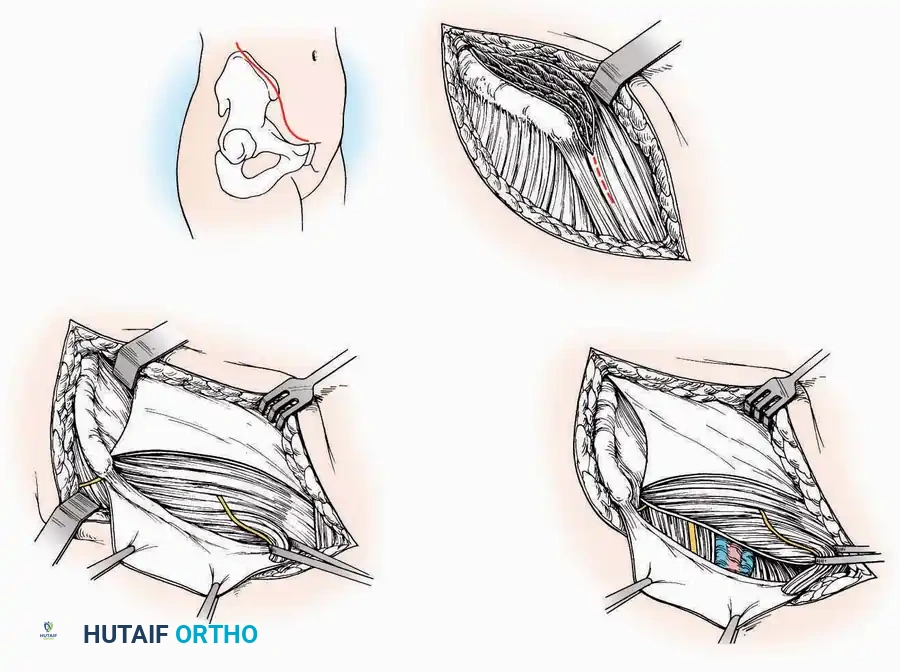

Surgical Technique:

* Incision: Begin over the anterolateral aspect of the leg, medial to the fibula and 5 cm proximal to the ankle joint line. Carry it distally over the joint, crossing the anterolateral aspect of the talar body and the calcaneocuboid joint, terminating at the base of the fourth metatarsal.

* Superficial Dissection: Incise the superficial fascia and the superior and inferior extensor retinacula down to the periosteum of the tibia and the ankle joint capsule.

* Vascular Ligation: This trajectory usually requires the identification and ligation of the anterolateral malleolar and lateral tarsal arteries.

* Nerve Protection: Retract the skin edges carefully. Identify and protect the intermediate dorsal cutaneous branches of the superficial peroneal nerve (SPN), which frequently cross the distal aspect of this incision.

* Muscle Management: Identify the origin of the extensor digitorum brevis (EDB) muscle on the lateral calcaneus. Divide it in the direction of its fibers, or detach its origin entirely and reflect it distally to expose the subtalar and calcaneocuboid joints.

* Deep Exposure: Retract the extensor digitorum longus (EDL) tendons, the dorsalis pedis artery, and the deep peroneal nerve (DPN) medially. Incise the anterior ankle capsule to expose the tibiotalar joint.

* Tarsal Exposure: Expose the talonavicular joint by dissecting deep to the extensor tendons and incising its capsule transversely. Continue laterally through the capsule of the calcaneocuboid joint. By excising the fat pad within the sinus tarsi (lateral and inferior to the talar neck), the posterior facet of the subtalar joint is brought into direct view.